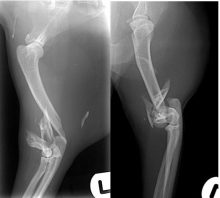

By Eastcott Referrals Orthopaedic Surgeon Fabio Frazzica A common cause of canine thoracic limb lameness in patients that are ...

Proximal Abducting Ulnar Osteotomy (PAUL) in dogs